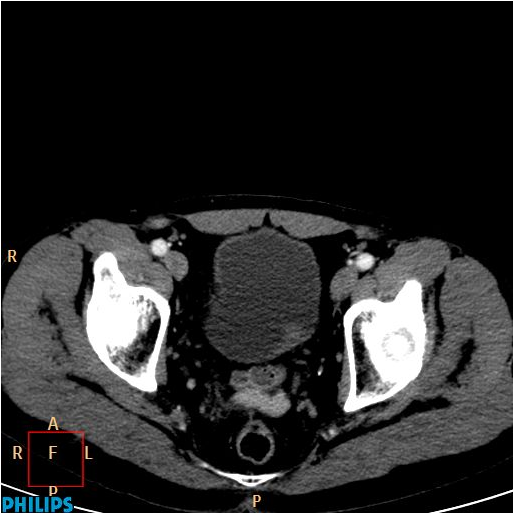

Image

Figure 12. Extensive right ovarian tumor.